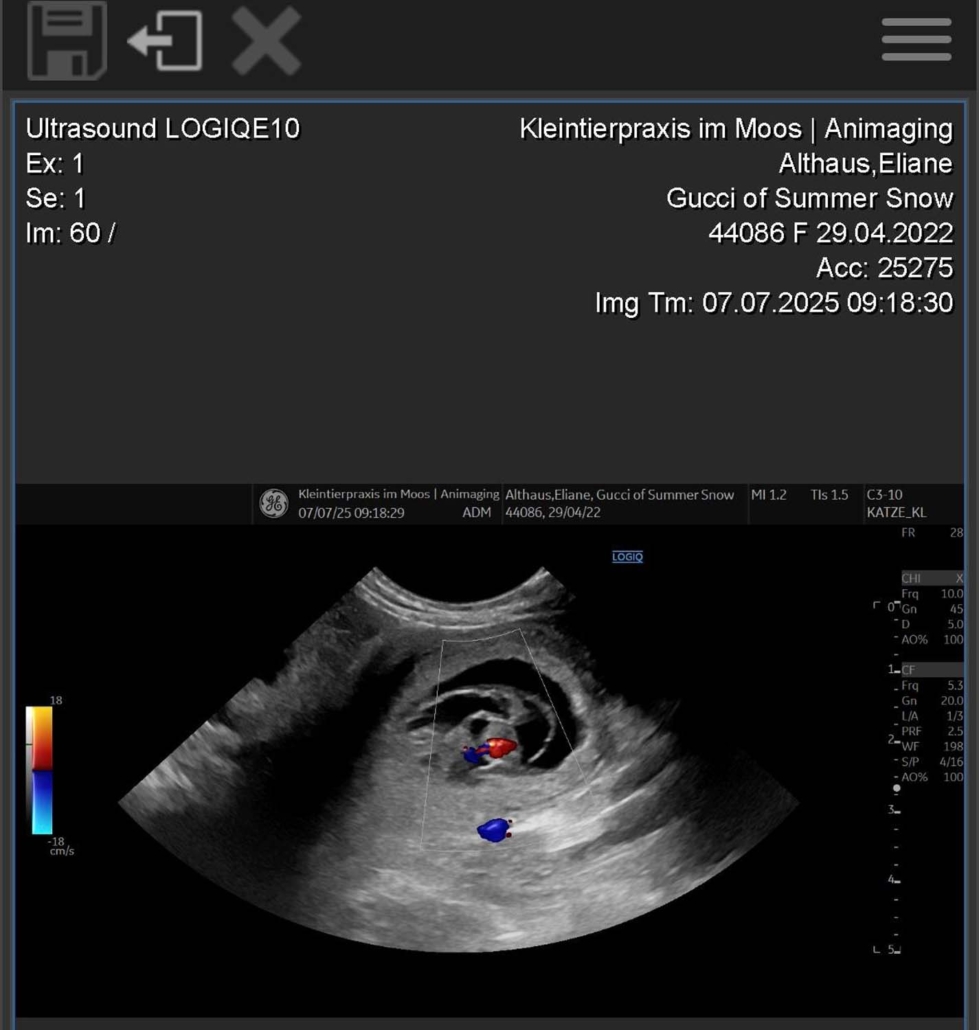

Gucci of Summer Snow | Geboren am 29.04.2022

Gucci ist trächtig – und wir freuen uns riesig auf Mitte August! Auf dem Röntgenbild sind vier kleine Parson Russell Terrier-Welpen zu erkennen! 🐶🐶🐶🐶